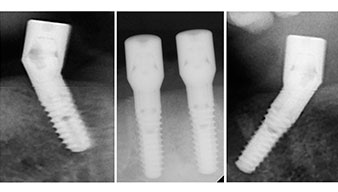

Направи се скенер с триизмерна компютърна томография (CBCT, Planmeca), за да се подпомогне планирането и да се намалят рисковете. Той показа, че качеството и количеството на наличната кост са достатъчни за операцията и имедиатното възстановяване, използвайки Fast & Fixed метод. Следвайки протокола за тази концепция, имплантите са поставени на 35, 32, 42 и 45 позиция. Ангулирането на дисталните импланти до 45° промени профила в задната зона и осигури по-голяма поддръжка в многоъгълната зона (Фиг. 3).

Ангулираните абатмънти (35°) са завити в имплантите, за да компенсират отклонението от дисталните импланти, така че в резултат профилът на разположение на всички импланти да е възможно най-перпендикулярен на нивото на захапката. Това е предпоставка за оклузално поставяне на временна и впоследствие на постоянна протеза (Фиг. 15 и 16).